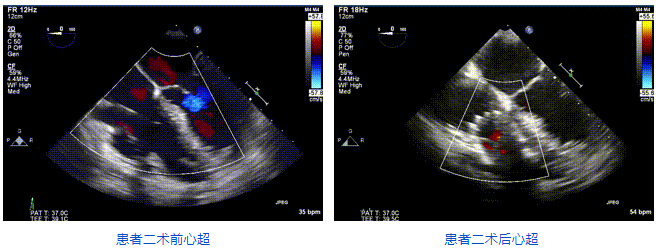

2021年12月24日,復(fù)旦大學(xué)附屬中山醫(yī)院葛均波院士團(tuán)隊(duì)成功應(yīng)用LuX-Valve Plus為一例極重度三尖瓣反流(TR)合并房顫、房缺的患者完成了經(jīng)血管三尖瓣置換術(shù),這是在前基礎(chǔ)上,本周完成的第三例經(jīng)血管三尖瓣置換手術(shù),葛均波院士、周達(dá)新教授等與心外科魏來教授、賴顥教授,心超室的潘翠珍教授、李偉教授及麻醉科的郭克芳教授共同完成了本周手術(shù),均獲得圓滿成功!患者術(shù)后超聲顯示無TR,臨床癥狀明顯改善。本周手術(shù)的成功也為L(zhǎng)uX-Valve Plus救治性臨床研究添上了濃墨重彩的一筆。

三例患者入院后,葛均波院士團(tuán)隊(duì)周達(dá)新教授、潘文志教授、張?jiān)床┦俊㈥惿┦考靶某业呐舜湔浣淌?、李偉教授?duì)患者的情況進(jìn)行詳細(xì)評(píng)估和討論,最終決定為三例患者選擇LuX-Valve Plus40mm、50mm和50mm型號(hào)的瓣膜進(jìn)行手術(shù)治療。手術(shù)后即刻拔除氣管插管,術(shù)后患者三尖瓣反流癥狀得到顯著改善,復(fù)查心超結(jié)果顯示人工三尖瓣瓣膜支架固定穩(wěn)定,瓣葉關(guān)閉形態(tài)未見異常,未見明顯反流。